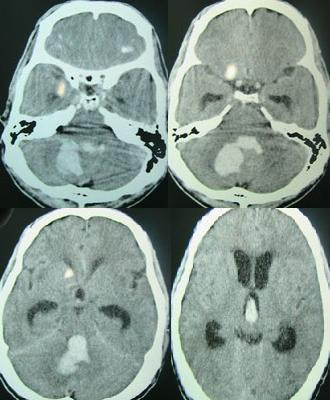

Subarachnoid Hemorrhage

Subarachnoid hemorrhage is hemorrhage that involves the subarachnoid area of the brain.

Subarachnoid hemorrhage symptoms include:

- Sudden “thunder clap” headache

- Worst headache of life

- Suddenly neck stiffness

Causes of subarachnoid hemorrhage include:

- Berry aneurysm rupture (85% of cases)

- Arteriovenous (AV) abnormalities

- Anticoagulation complication